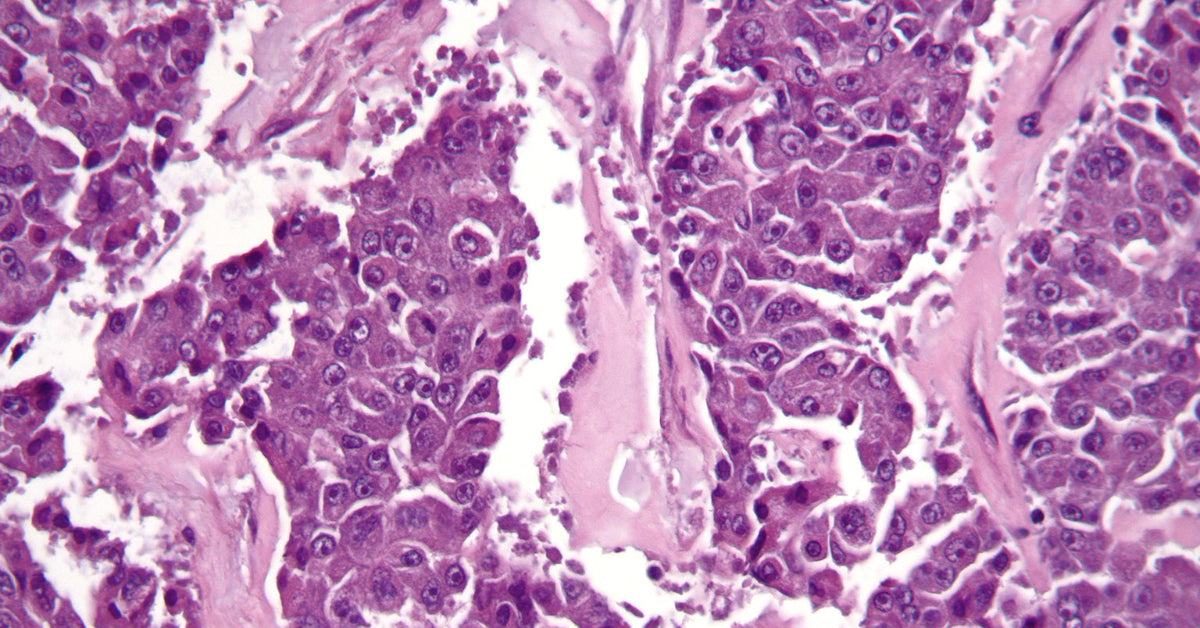

I started with this cell image, or histology slide, of Pancreatic Cancer. As a side note, I'm glad this image comes in purple because it's the awareness color for pancreatic cancer.

This necklace features an adjustable sterling silver or 14k gold filled chain that can be worn at any length from 16-18 inches. The large round pendant is a cutout from a Pancreatic Cancer cell image coated in resin. A lobster clasp makes sure this chain will stay on all day long.